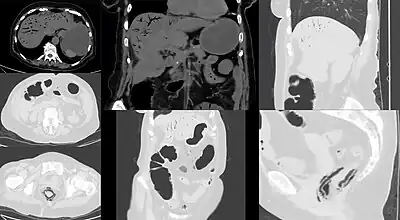

CT image showing mesenteric ischemia with pneumatosis intestinalis and gas in mesenterial and liver veins

Computed tomography (CT scan) is often used.[29][30] The accuracy of the CT scan depends on whether a small bowel obstruction (SBO) is present.[31]

Early findings on CT scan include:

• Intestinal mesenteric edema[29]

• Bowel dilatation[29]

• Bowel wall thickening[29]

• Intestinal mesenteric stranding[32]